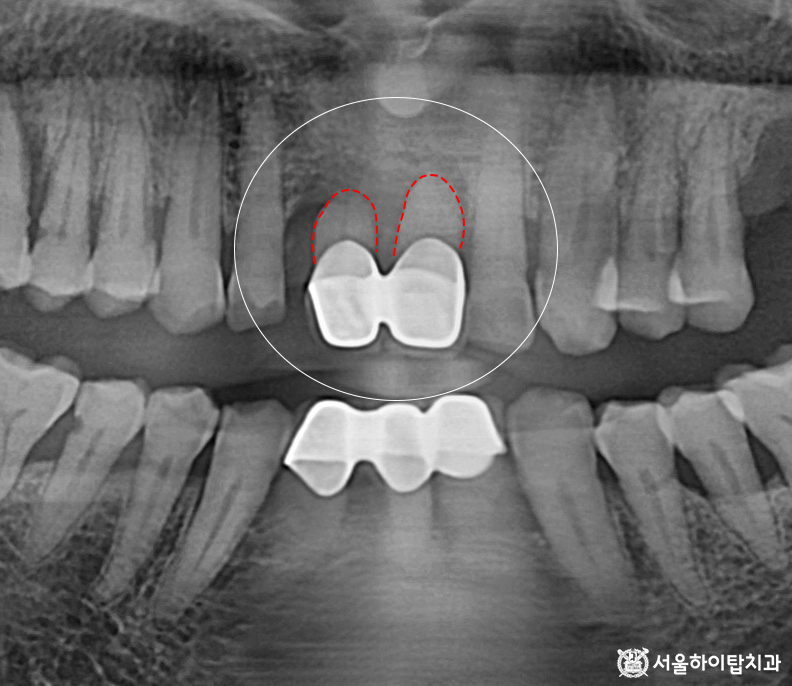

또한 앞니 부위를 다시 살펴보면

크라운이 수복되어 있는 모습을

확인할 수 있습니다.

그러나 치근 길이가 짧아진 상태이며,

주변 치조골의 소실 또한 관찰됩니다.

이런 경우 치아를 지지해 주는

구조가 약해지기 때문에,

간석역 치과 에서는

치아가 흔들리는 동요도(Mobility)가

상당히 높을 것으로 예상됩니다.

즉, 치주조직의 지지력이

크게 감소한 상태이므로

일상적인 저작력만으로도

흔들리거나 파절, 탈락 위험이

높은 상황이라 할 수 있습니다.

2. 정밀한 3D-CT 검진

구치부는 어금니가 상실되어 있고,

앞니의 경우 치주 지지력이 부족해

동요도가 심한 상태이므로

임플란트가 필요한 상황입니다.